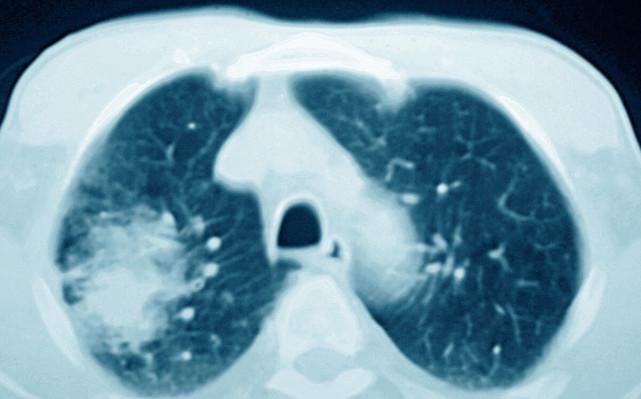

肺癌是一种恶性肺部疾病,早期肺癌可以通过手术根治,中晚期肺癌虽然也有一定的手术根治率,但大部分无法完全根治,只能保守治疗延长生命。

肺癌分四种基本的病理类型,分别是肺鳞癌,肺腺癌,大细胞肺癌,小细胞肺癌,前三者统称非小细胞肺癌,之所以这样分是因为这三者的生长,转移,治疗和预后与小细胞肺癌有显著的不同,当然治疗上也有很大的区别。

肺癌的治疗目前仍然以化疗、放疗为基本治疗,这两种对肿瘤细胞和正常细胞都有杀伤作用,所以不是精准治疗,而现在的癌症已经进入了精准治疗时代,在精准检测肿瘤细胞的基因突变类型以及免疫检查点表达的基础上,发展出了精准治疗方法,包括靶向治疗和免疫治疗。